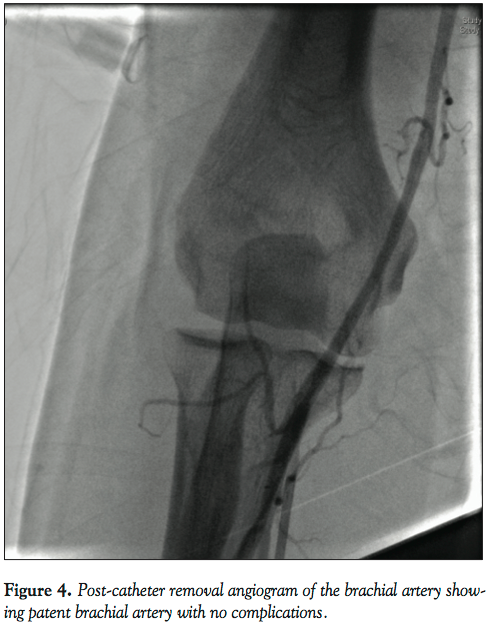

Fr JL4 catheter. Some spasm was encountered going up with the JL4. While clocking and advancing the catheter, we noticed damping of the arterial wave paralleled with inability to further manipulate the catheter. On fluoroscopy, the JL was found looped and kinked on itself in the brachial segment (Figure 1). Different maneuvers to de-loop it failed, including external fixation of the distal part of the catheter at the arm level both by putting circumferential pressure on the arm with our hands as well as by inflating the blood pressure cuff to a different level at the arm so it forms an anchor for us to untwist the loop. We could not even advance a coronary wire into that loop (Figure 2). Another cocktail was used in vain. To resolve our problem, we used the scalpel to cut the proximal part of the JL catheter. Next, we exchanged the 6 Fr 12 cm sheath with a 5 Fr long sheath while the severed and trapped JL4 catheter served as a guidewire. We advanced the sheath up to the anticubital fossa (Figure 3). Under fluoroscopy, we gently pulled the trapped catheter. It smoothly unfolded its loop while slipping into the long sheath, hence freeing the catheter. It is important to mention here that complete inability of the catheter to move due to kink/loop can be a limitation of this technique. Dye was then injected in the catheterless sheath to confirm patency of the brachial artery. We had contemplated using a larger French sheath in lieu of the 5 Fr one based on the fact that the loop has a better chance of slipping into the wider lumen of the larger sheath. The problem was that the introducer of the 6, 7, or 8 Fr sheaths would not go over the 5 Fr catheter, which was thicker than the wire. Also, it would have been incautious to push any of these sheaths without their respective introducer directly over the trapped catheter, which would, at the least, risk stripping the arterial intima. Because of the resulting spasm in the radial artery, the procedure was switched to femoral. Three months later, the patient still has his radial and ulnar pulses in his right hand and no long-term complications were noted. To our knowledge, this is the first description of this method in removing the looped cardiac catheter from the radial access.